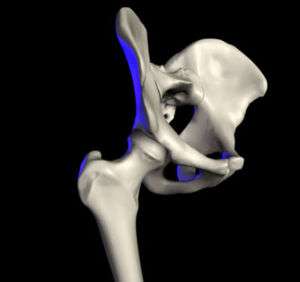

The hip joint is a synovial joint formed by the articulation of the rounded head of the femur and the cup-like acetabulum of the pelvis. It forms the primary connection between the bones of the lower limb and the axial skeleton of the trunk and pelvis. Both joint surfaces are covered with a strong but lubricated layer called articular hyaline cartilage. The cuplike acetabulum forms at the union of three pelvic bones — the ilium, pubis, and ischium.[5] The Y-shaped growth plate that separates them, the triradiate cartilage, is fused definitively at ages 14–16.[6] It is a special type of spheroidal or ball and socket joint where the roughly spherical femoral head is largely contained within the acetabulum and has an average radius of curvature of 2.5 cm.[7] The acetabulum grasps almost half the femoral ball, a grip augmented by a ring-shaped fibrocartilaginous lip, the acetabular labrum, which extends the joint beyond the equator.[5] The head of the femur is attached to the shaft by a thin neck region that is often prone to fracture in the elderly, which is mainly due to the degenerative effects of osteoporosis.

The capsule attaches to the hip bone outside the acetabular lip which thus projects into the capsular space. On the femoral side, the distance between the head's cartilaginous rim and the capsular attachment at the base of the neck is constant, which leaves a wider extracapsular part of the neck at the back than at the front.[16] [17]

The strong but loose fibrous capsule of the hip joint permits the hip joint to have the second largest range of movement (second only to the shoulder) and yet support the weight of the body, arms and head.

The hip joint is reinforced by four ligaments, of which three are extracapsular and one intracapsular.

The extracapsular ligaments are the iliofemoral, ischiofemoral, and pubofemoral ligaments attached to the bones of the pelvis (the ilium, ischium, and pubis respectively). All three strengthen the capsule and prevent an excessive range of movement in the joint. Of these, the Y-shaped and twisted iliofemoral ligament is the strongest ligament in the human body. [17] In the upright position, it prevents the trunk from falling backward without the need for muscular activity. In the sitting position, it becomes relaxed, thus permitting the pelvis to tilt backward into its sitting position. The iliofemoral ligament prevents excessive adduction and internal rotation of the hip. The ischiofemoral ligament prevents medial (internal) rotation while the pubofemoral ligament restricts abduction and internal rotation of the hip joint. [18] The zona orbicularis, which lies like a collar around the most narrow part of the femoral neck, is covered by the other ligaments which partly radiate into it. The zona orbicularis acts like a buttonhole on the femoral head and assists in maintaining the contact in the joint. [17] All three ligaments become taut when the joint is extended - this stabilises the joint, and reduces the energy demand of muscles when standing [19]

The intracapsular ligament, the ligamentum teres, is attached to a depression in the acetabulum (the acetabular notch) and a depression on the femoral head (the fovea of the head). It is only stretched when the hip is dislocated, and may then prevent further displacement. [17] It is not that important as a ligament but can often be vitally important as a conduit of a small artery to the head of the femur, that is, the foveal artery.[20] This artery is not present in everyone but can become the only blood supply to the bone in the head of the femur when the neck of the femur is fractured or disrupted by injury in childhood.[21]